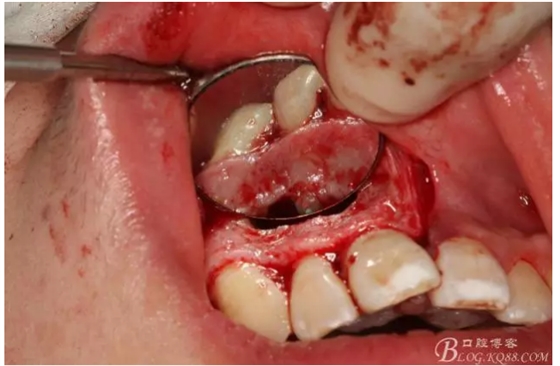

圖5.清理骨腔,可以看到12的根尖暴露在骨腔內(nèi)。

圖6.超聲骨刀切除根尖3mm。